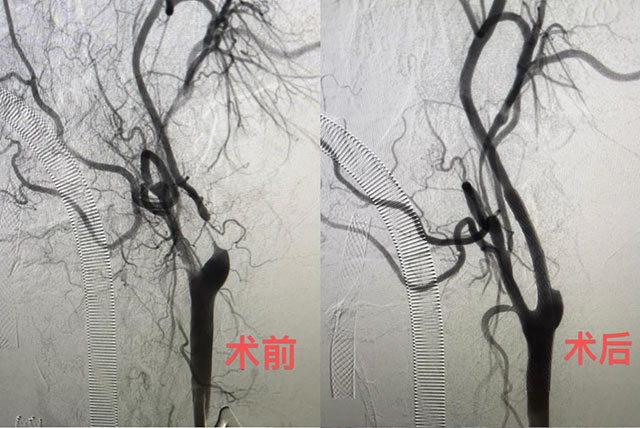

6月11日,该院神经外科陈光忠主任医师、秦琨副主任医师联合神经内科代成波主任团队,在神经电生理室、麻醉科和手术室等科室支持下,成功开展颈动脉狭窄治疗的全新术式:经颈动脉血运重建术(TCAR)。颈部开口仅2厘米,血流阻断15分钟,整个手术仅用时一小时便顺利完成。术后从影像结果可见,术前已经几乎断裂的血运通道,术后血运立即恢复。6月13日,术后2天的李大叔就已顺利出院。

前后对比,颈动脉重新被“打通”